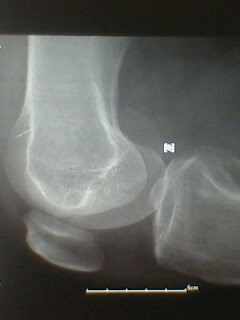

标题: X5658:膝关节改变?!

中年男性,外伤,疼痛!

股骨下段骨软骨瘤。撕脱性骨折

支持考虑骨软骨瘤,髁上突在肱骨内髁上方.本例股骨外髁关节面似有异常,但是可以是与髌骨重叠构成,必要时加照正位(稍内斜一点把髌骨让开)

宽基底与股骨干相连,背离关节面,支持考虑股骨下段外生骨疣

宽基,无指状突起,考虑外生骨疣。

外侧髁撕脱性骨折,骨软骨瘤。